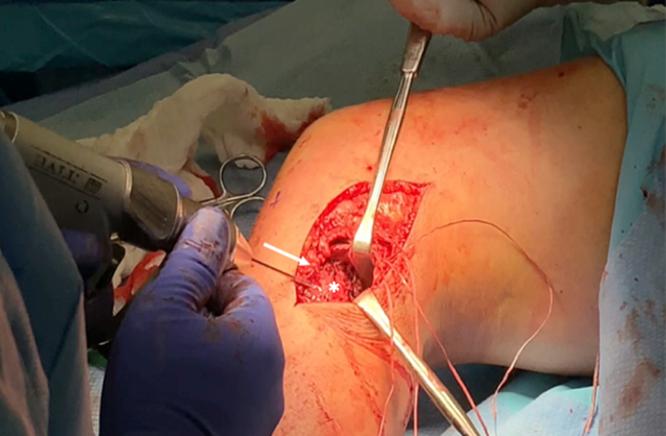

Injuries to the lateral collateral ligament (LCL) most commonly occur with concomitant cruciate ligament tears. Over the past decade, there has been increased interest in anatomic reconstruction of the posterolateral corner (PLC). Not much attention has been paid to anatomic primary LCL repair given the historically high failure rates of primary repair of lateral sided knee ligaments, but better outcomes can now be expected because of recent developments in additional suture augmentation. The purpose of this Technical Note is to describe the surgical technique of primary distal LCL repair using suture augmentation. Using this procedure, the native ligament is preserved while allowing early mobilization as suture augmentation is protective of the repaired ligament.

外侧副韧带(LCL)损伤最常伴有交叉韧带撕裂。在过去十年中,人们对后外侧角(PLC)的解剖重建越来越感兴趣。鉴于历史上外侧膝关节韧带一期修复的失败率较高,一期LCL解剖修复并未得到太多关注,但由于近期在额外缝线增强方面的进展,现在可以期待更好的结果。本技术说明的目的是描述使用缝线增强进行LCL远端一期修复的手术技术。采用该手术方法,可保留天然韧带,同时由于缝线增强对修复韧带具有保护作用,可实现早期活动。